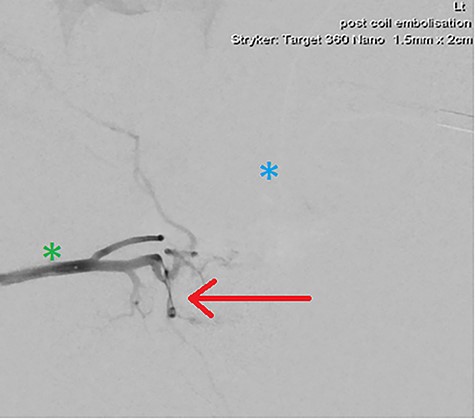

DSA demonstrating significantly reduced flow into the cavernosal artery pseudoaneurysm post-coil embolization (red arrow); note the left (blue asterix) and right (green asterix) distal branches of bilateral internal pudendal arteries for reference.